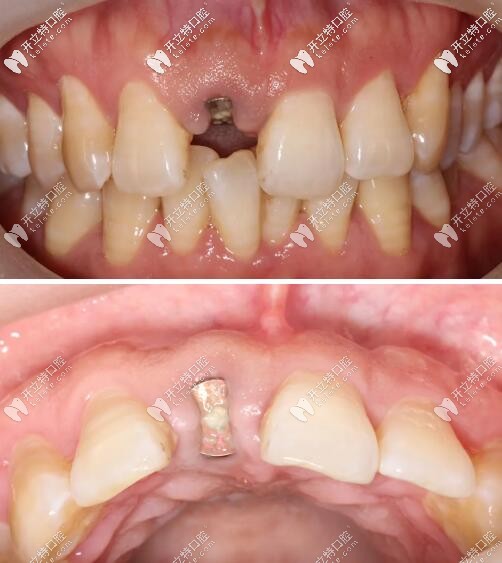

訴求:31歲男性1天前不慎摔倒致右上前牙疼痛、松動,要求治療

口內(nèi)檢查

被磕的11號牙(門牙)切端1/3折斷,并見不規(guī)則縱向裂紋;

牙齦色粉、質(zhì)韌,無明顯紅腫,牙齦乳頭充盈。

術(shù)后佩戴活動義齒恢復美觀;

活動義齒修復門牙